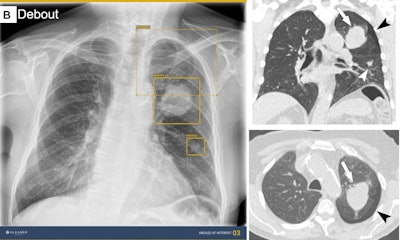

AI detected a lung mass, a lung nodule, and a small pneumothorax. Without AI assistance, only one thoracic radiologist and one general radiologist detected all abnormalities, whereas with AI assistance, one thoracic radiologist, two general radiologists, and one resident detected all abnormalities. Corresponding coronal and axial CT images show the lung mass (arrows), the lung nodule (white arrowheads), and the small pneumothorax (black arrowheads) that should have been detected on the chest radiograph. Image courtesy of Radiology.